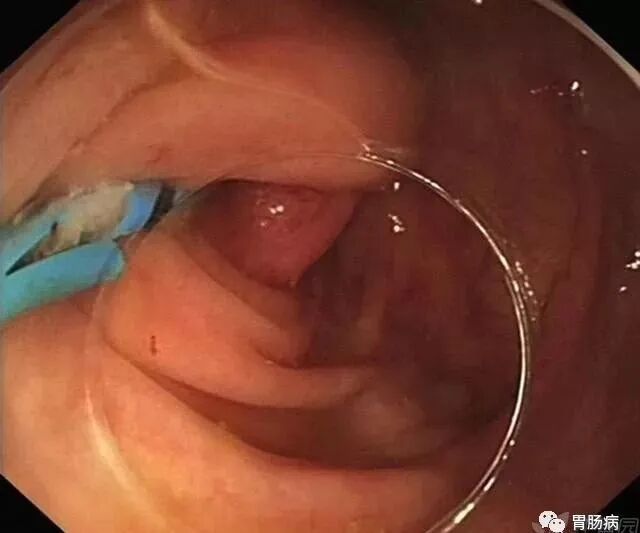

通过内镜下置入球囊导管或取石网篮,将粪石取出,原理如ERCP取石术。(黑箭头示取出的粪石)。

在充分取出粪石后,置入塑料支架行脓液引流及进一步阑尾腔冲洗(生理盐水+抗生素)。